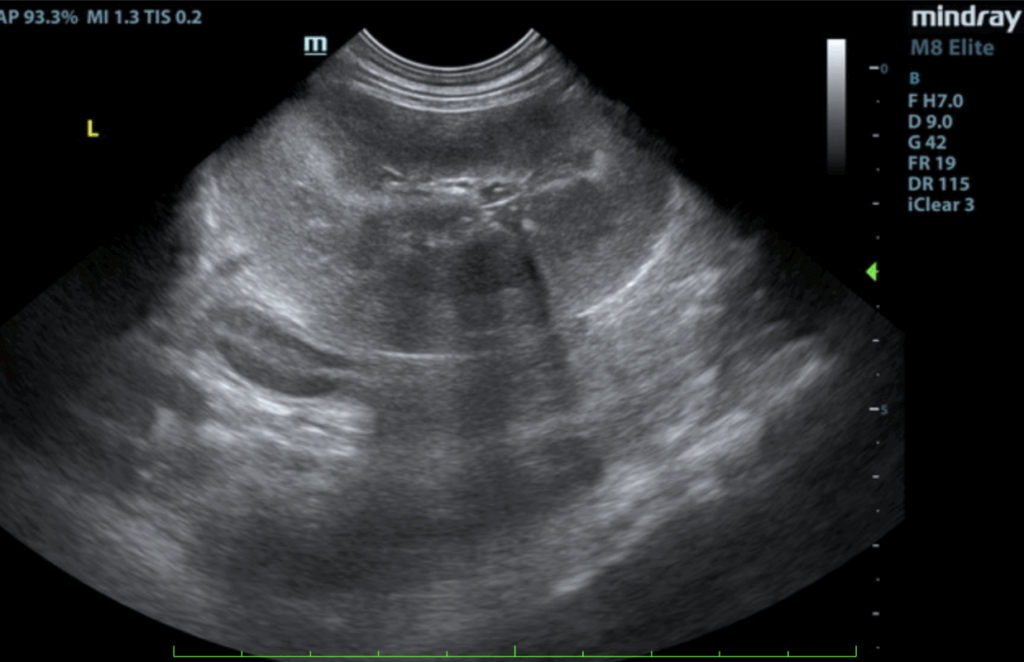

Liver:

The liver was subnormal in size. The mid dorsal liver in this patient revealed an abnormal intrahepatic branch of the portal vein. This is most consistent with central divisional shunt. However, this should be further evaluated with CT. The gallbladder and common bile duct were unremarkable.

- Intrahepatic shunt – suspect central divisional or right divisional shunt